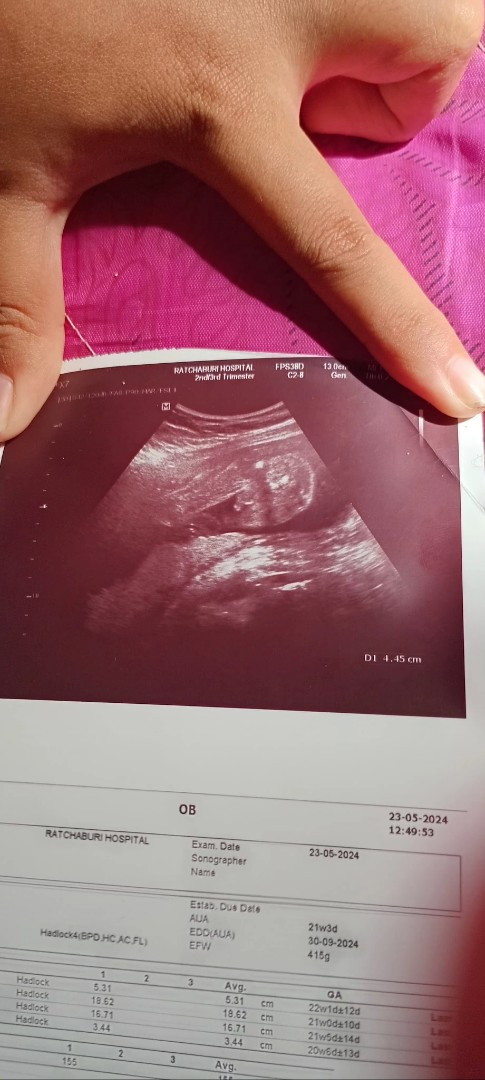

ตอนไปฝากครรภ์เลยค่ะ ตอนนี้26+5wแย้ววววว